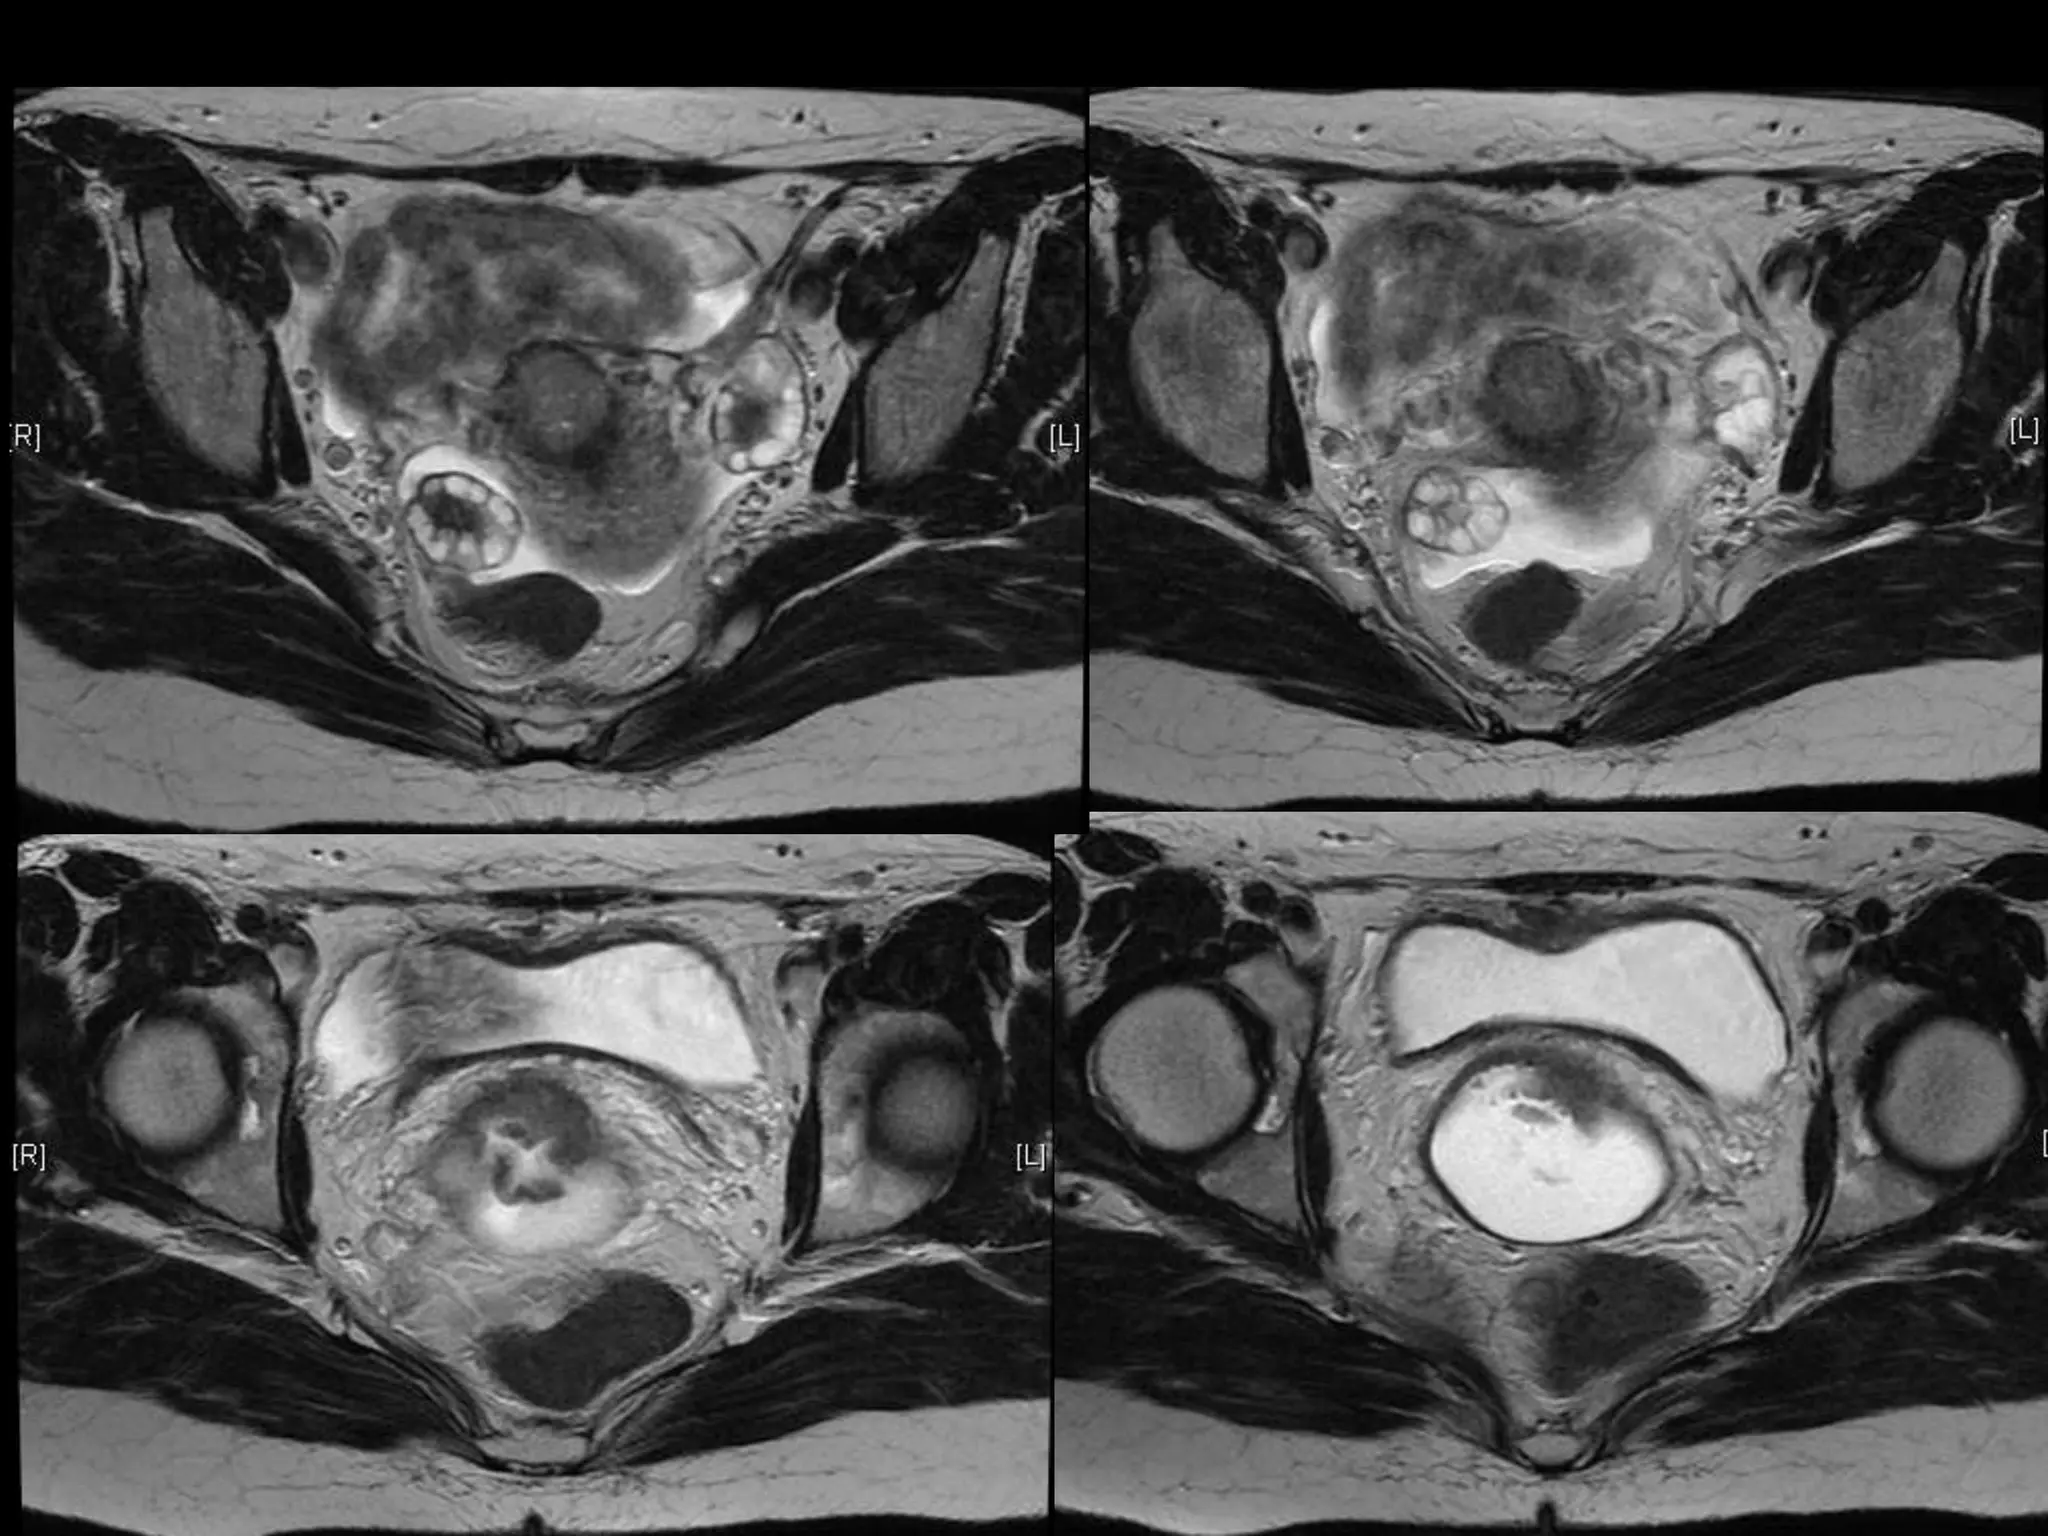

HISTORY

โ€ข   42 yo female

โ€ข   Recent immigrant from China

โ€ข   C/O postcoital and intermenstrual bleeding

โ€ข   Abnormal GYN exam

โ€ข   Abnormal biopsy

โ€ข   Further imaging performed

MRI findings - Stage IIB

with PET/CT - Stage IIIB

HISTORY โ€ข 42 yo female โ€ข Recent immigrant from China โ€ข C/O postcoital and intermenstrual bleeding โ€ข Abnormal GYN exam โ€ข Abnormal biopsy โ€ข Further imaging performed

MRI findings -Stage IIB with PET/CT - Stage IIIB Cervical Cancer